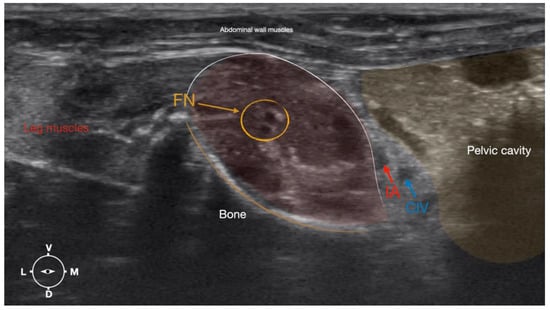

3.1.2. Femoral Nerve

The femoral nerve was found in the substance of the IPM with a dorso-ventral trace (Figure 8). It was divided into branches before it left the substance of the IPM to enter the leg through the vascular and muscular lacuna.

Based on the anatomical dissection and the US scans performed in this phase, the best way to locate and inject the FN was achieved by scanning the IPM from the projection of the iliac crest in the caudal direction. Ultrasonographically, the femoral nerve appeared as a hypoechoic structure in the dorsal part of the IPM, becoming hyperechoic/honey-comb-like in the ventral part of the mentioned muscle. The IPM was displayed as structures with heterogeneous echogenicity. The ilium and the vertebrae were displayed as a hyperechoic structure with acoustic shadow and located lateral and dorsal to the femoral nerve, respectively.

Figure 4. Corresponding transverse ultrasound image to Figure 5. The window of interest was set at a depth of 2 cm and the focus was at the level of the femoral nerve to optimize the image quality. The ultrasound image shows the FN and related structures. IA, iliac artery, CIV, common iliac vein; FN, femoral nerve; D, dorsal; L, lateral; M, medial; V, ventral.